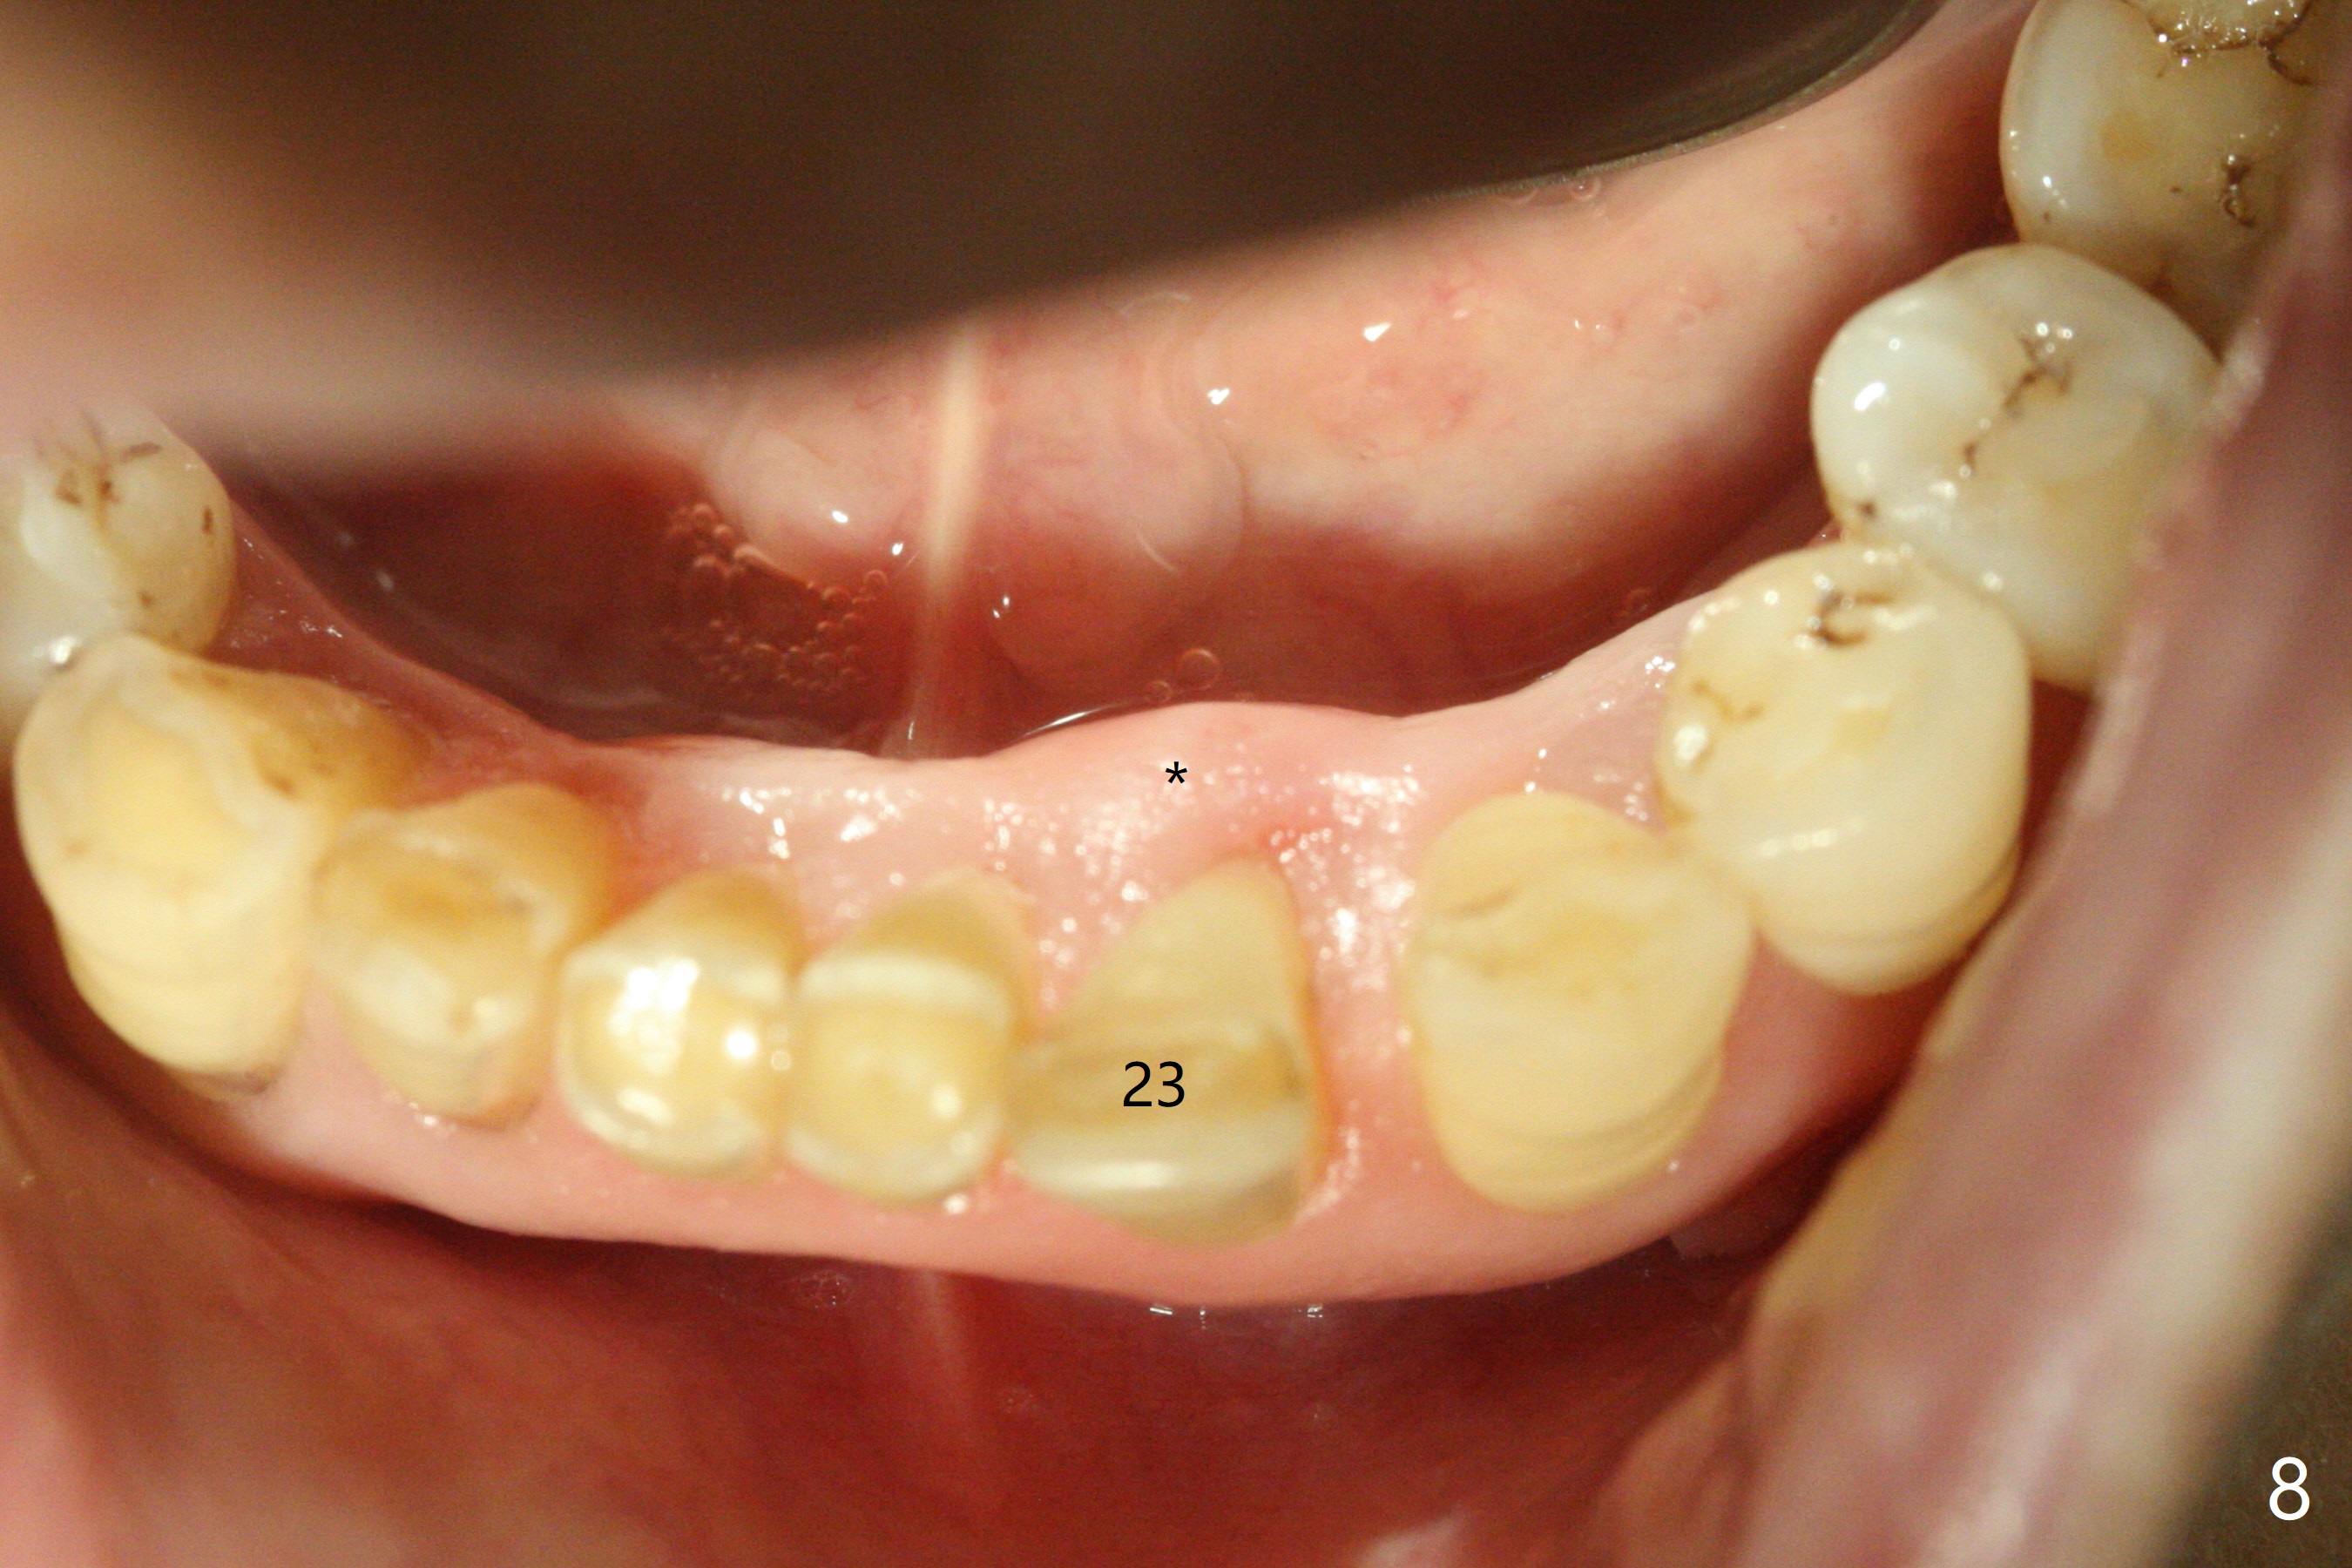

A 73-year-old woman has discomfort associated with #23 four months post Class V composite at #23-25 (Fig.1 C (*: Class V lesions)). Bone loss seems to be more severe lingually, especially at the crest (Fig.2 L). It appears that the apex of the tooth #24 is also in the large apical lesion (Fig.3). Class V composite is apparently continuous with the pulp at #25,24,23 (Fig.5-7). In contrast, Class V defect does not involve the pulp at #26 (Fig.4). If necrosis is confirmed clinically for #23 24 and 25, RCT will be conducted. Due to 7-day Amoxicillin taken for #3 implant, the patient feels that her tongue moves freely, as related to reduction in pain and swelling lingual to #23 (Fig.8 *). Endo ice test shows necrosis of #23 to 25. RCT is initiated at #23 (Fig.9) with buccal and lingual swelling. Endo may have to be at #24 with apicoectomy with PRF. The lingual swelling remains at #23, although there is no pain or purulent discharge 5 and 5.5 months post debridement (Fig.10,11). RCT is finished (Fig.12). Apicoectomy is pending with PRF. Less aggressive curettage will be done at #24 to maintain apical blood supply. Vitality tests have been done without conclusion.